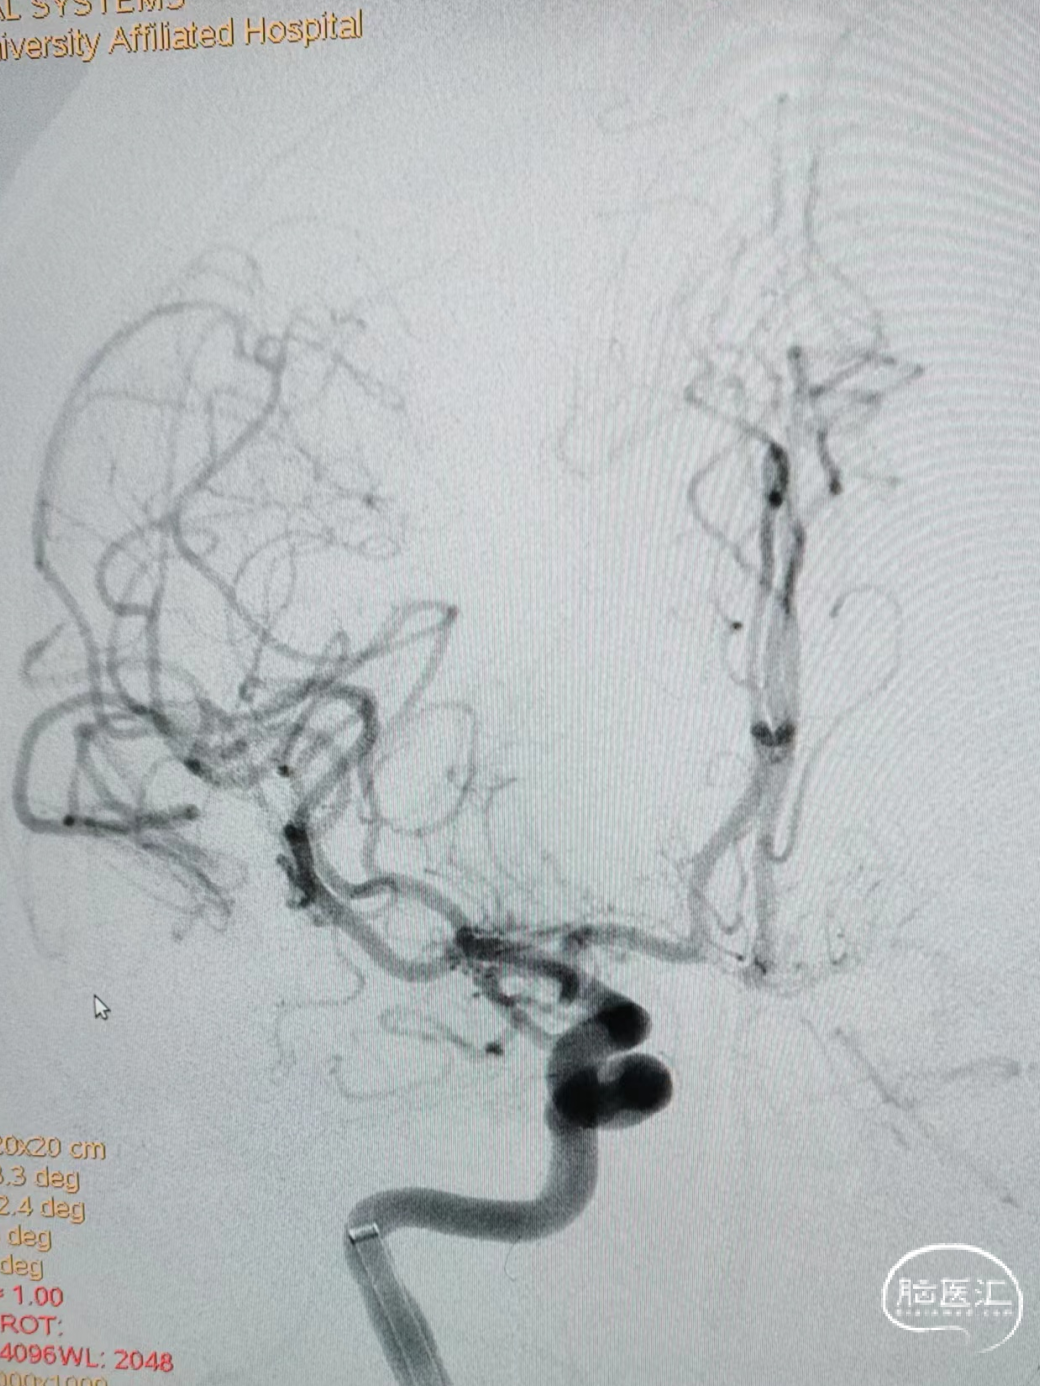

一次支架取栓后血管完全通畅,达到mTICI 3级。

可见取出血栓量较大,在支架远端抓捕篮内有部分细小血栓被成功捕获。

术后即刻影像可见血管完全通畅,达到mTICI 3级。